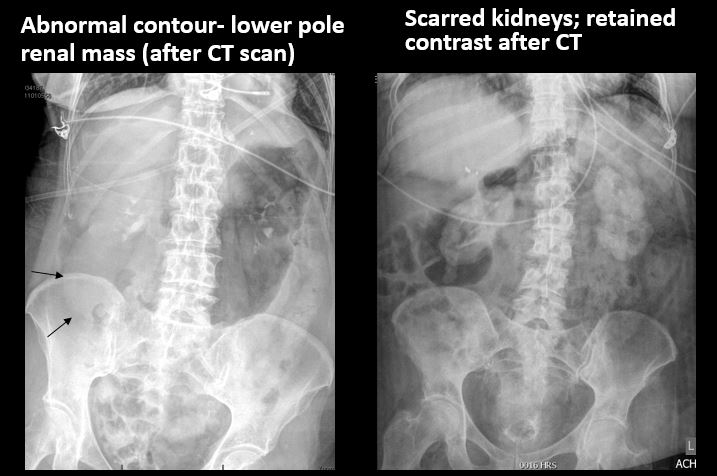

There is an abnormality of the size or contour of the right and/or left kidney. |

No | NA |